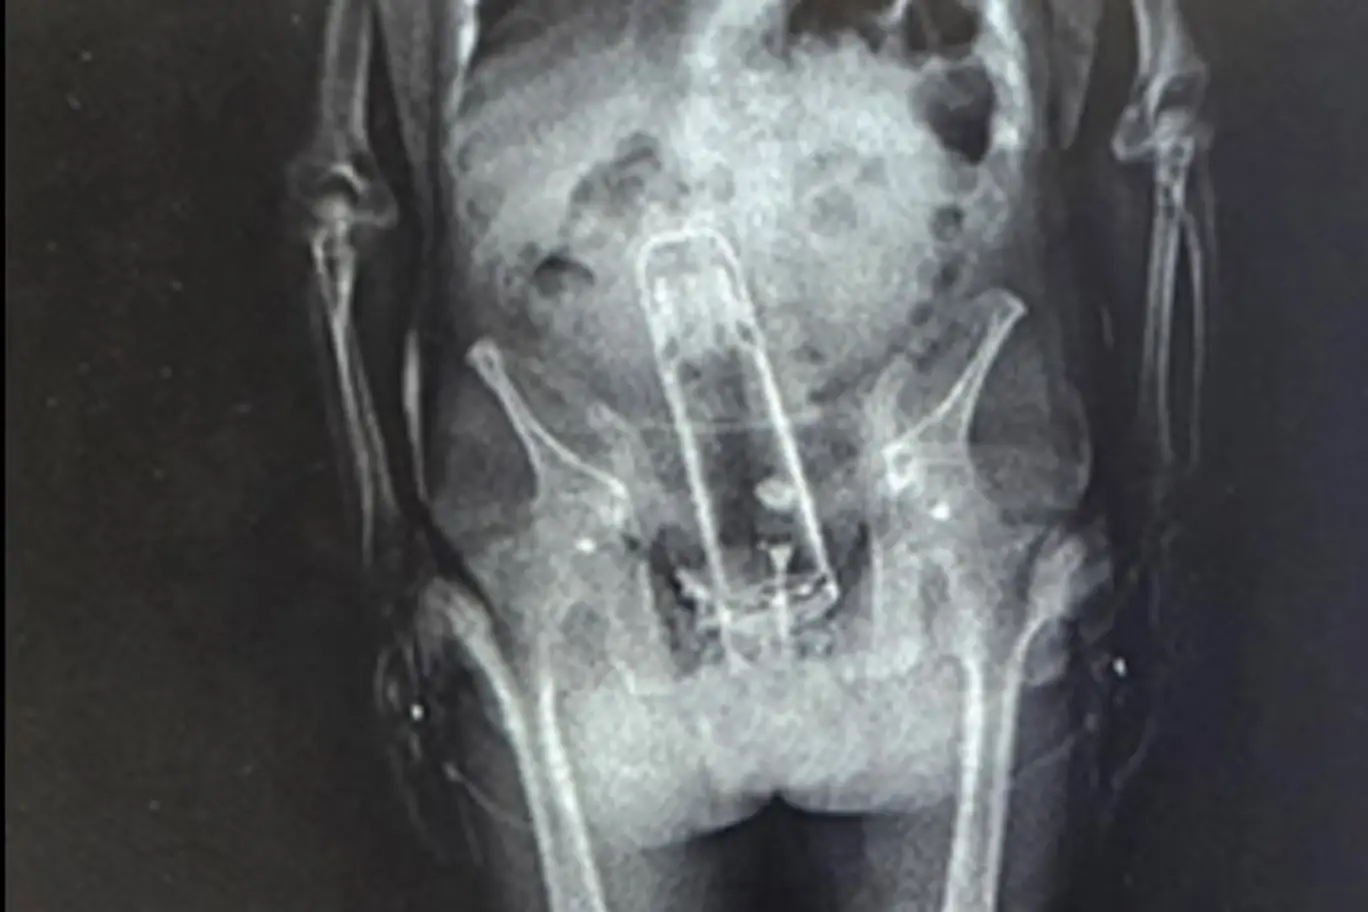

Arrested and taken to jail, the Florida man was put through a customary X-ray scan to detect whether or not he had anything untoward on him,or, in this case, in him.

Officers claimed they'd already found meth on the man when they brought him in, and when they gave him the body scan they saw, well, see for yourself...

That is a Thermos flask lodged firmly up the man's bum, with Sheriff Grady Judge saying: "He brought a thermos into the jail. That’s right.